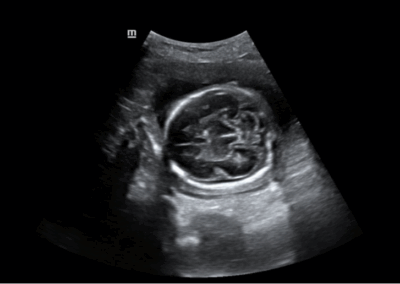

Los sistemas ecográficos estándares disponibles en la actualidad generalmente permiten un diagnóstico básico, pero carecen de funcionalidades avanzadas. Ahora, el DC-30 FullHD es la respuesta perfecta para un rendimiento de imagen de alta calidad, con una pantalla táctil de 21,5 pulgadas y funciones avanzadas como Auto IMT, iScape, elastografía Natural Touch, imágenes con contraste UWN e imágenes Doppler tisulares en el ámbito de las imágenes generales, y Smart OB, Smart face e iLive en el ámbito de la obstetricia.